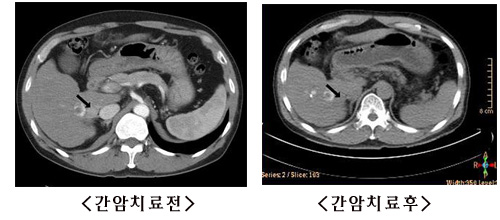

Áö³ 2003³â °£¾Ï Áø´ÜÀ» ¹Þ°í Ä¡·á¸¦ ¹ÞÀº ÀûÀÌ ÀÖ´Â 57¼¼ÀÇ ±è ¸ð¾¾(³²)¾¾´Â Áö³ 1¿ù CTÃÔ¿µÀ» ÇÑ °á°ú ¶Ç´Ù½Ã ¾ÏÀÌ Àç¹ßÇÑ »ç½ÇÀ» ¾Ë°Ô µÇ¾î Áö³ 2¿ù °Ç¾ç´ëÇб³º´¿øÀ» ã¾Ò°í, »çÀ̹ö³ªÀÌÇÁ°¡ µµÀ﵃ ¶§±îÁö ±â´Ù·È´Ù°¡ Áö³ 4¿ù 10ÀÏ ½Ã¼úÀ» ¹Þ¾Ò´Ù. ±× °á°ú 2.5§¯ÀÇ Å©±â¿´´ø °£¾ÏÀº PET CT·Î È®ÀÎÇÑ °á°ú ÀÚÃ븦 ãÀ» ¼ö ¾ø°Ô µÇ¾úÀ¸¸ç, ´õ È®½ÇÇÑ °á°ú¸¦ È®ÀÎÇϱâ À§ÇØ 6¿ù10ÀÏ CTÃÔ¿µÀÌ ¿¹¾àµÇ¾î ÀÖ´Ù.(»çÁø ÂüÁ¶)